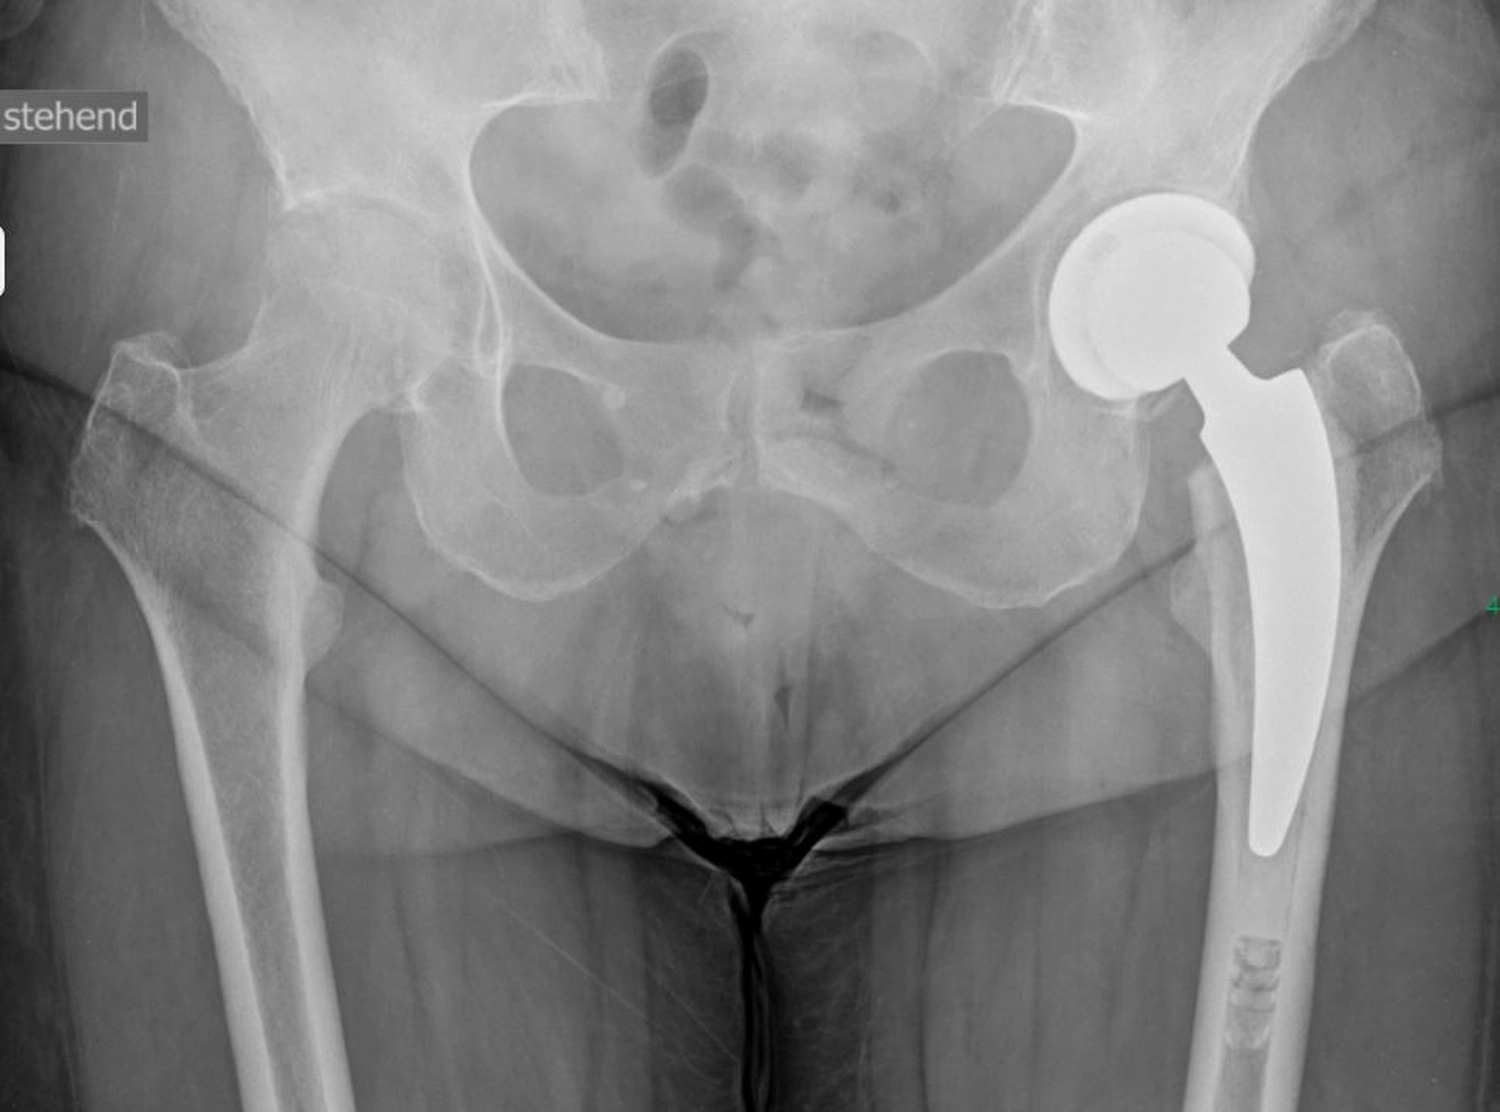

Das Hüftgelenk ist eines der größten und am stärksten belasteten Gelenke des menschlichen Körpers. Mit zunehmendem Alter oder durch Erkrankungen kann es zu einem Verschleiß (Arthrose) oder zu Schädigungen des Gelenkes kommen, die starke Schmerzen und Bewegungseinschränkungen verursachen. Sofern konservative Behandlungen wie Schmerzmedikamente, Krankengymnastik oder Injektionen nicht mehr ausreichen, kann der Ersatz des Hüftgelenkes durch eine Endoprothese notwendig werden.

Ein künstliches Hüftgelenk ersetzt die geschädigten Teile des natürlichen Gelenkes. Es besteht aus mehreren Komponenten, die gemeinsam ein neues, stabiles und bewegliches Gelenk bilden. Die Pfanne wird in das Becken eingesetzt. Der Schaft wird im Oberschenkelknochen verankert. Der Prothesenkopf sitzt oben auf dem Schaft und bildet die „Kugel“ des Gelenkes und bewegt sich reibungsarm in der Pfanne.

Je nach Knochenqualität und Alter der PatientInnen werden zwei Verfahren angewendet.

Bei der zementfreien Prothese werden der Schaft und die Pfanne fest eingepresst und eingeschlagen. Der Knochen wächst in die aufgeraute Oberfläche ein und fixiert die Prothese dauerhaft.

Bei der zementierten Prothese werden die Prothesenteile mit einem speziellen Knochenzement befestigt. Der Vorteil besteht in einer sofortigen Stabilität, besonders geeignet bei älteren oder osteoporotischen PatientInnen.

Daneben gibt es sog. Hybridverankerungen, z. B. Pfanne zementfrei, Schaft zementiert.

Moderne Prothesen, wie wir sie hier in Stenum verwenden, sind so konstruiert, dass sie reibungslos, stabil und langlebig funktionieren, meist über viele Jahre bzw. Jahrzehnte (15–20 Jahre).

Dank der modernen Materialien und gewebeschonenden Techniken des Einbringens, (minimalinvasiver Zugang) ist die Hüft-TEP heute ein sehr erfolgreicher Eingriff, der vielen Menschen eine deutliche Verbesserung ihrer Lebensqualität ermöglicht.